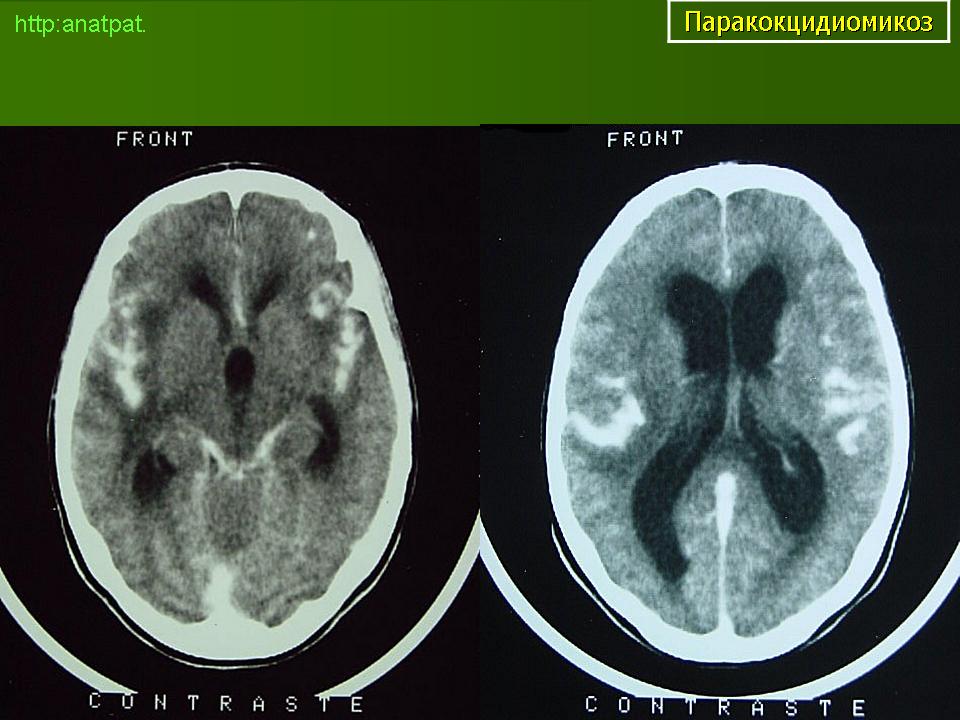

ГМ. Паракокцидиомикоз. +

Паракокцидиомикоз.

Множественные "узловые образования" имитирующие метастазы.